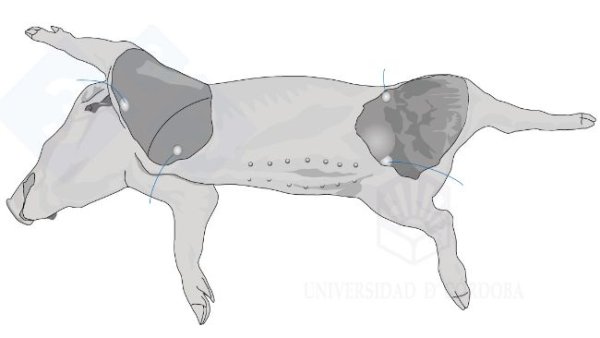

Empezamos una nueva sección, coordinada por el equipo de anatomía patológica de la Universidad de Córdoba, que nos mostrará, de una forma muy visual y práctica, como llevar a cabo una necropsia en un cerdo.

En esta segunda entrega vemos la extracción del conjunto lengua-tráquea-pulmones-corazón. Extraeremos los órganos de la cavidad abdominal, tanto del sistema digestivo como del aparato urinario y genital. En la cabeza accederemos a los cornetes nasales y el cerebro y cerebelo.

Mientras que en las dos primeras entregas hemos abordado la necropsia en decúbito lateral, en esta tercera entrega explicaremos como hacer la necropsia en decúbito supino.